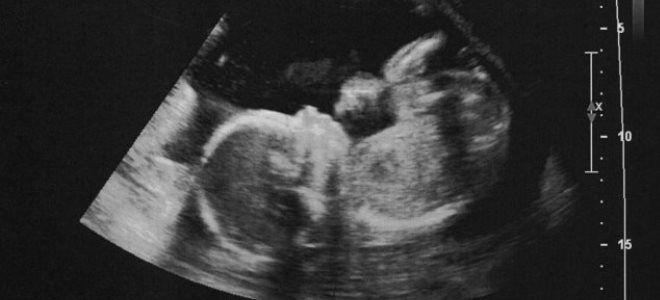

Для женщин, которые еще не проходили УЗИ во втором триместре, на 21 неделе беременности проводится данное исследование. Во время процедуры врач анализирует показатели развития плода и состояние плаценты.

Среди исследуемых показателей:

- расположение плаценты;

- объем околоплодных вод.